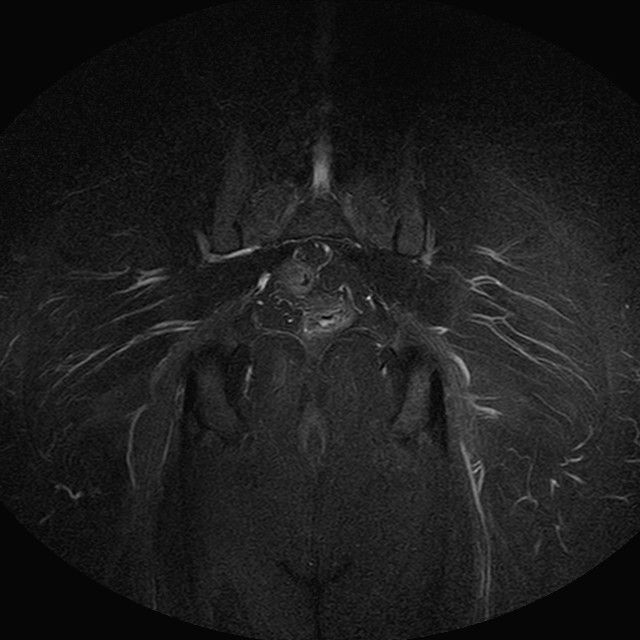

Esami: RMN BACINO

eSTIR

Evidenti e simmetriche alterazioni osteofitosiche in regione coxo femorale con riduzione delle rime articolari. Degenerazione completa del cercine glenoideo. Non attuali segni di versamento articolare. Non segni di edema osseo che escludono attuale algodistrofia od osteonecrosi. Lieve e simmetrica riduzione del trofismo della muscolatura glutea.